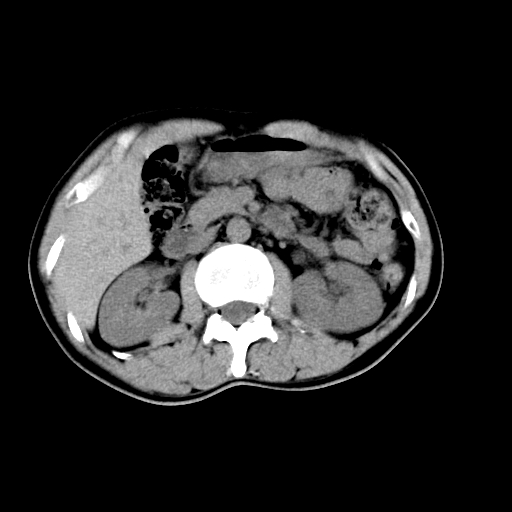

男,47岁,左输尿管结石碎石治疗后10余日。彩超示:左输尿管下段狭窄、输尿管积水。请各位讨论一下左输尿管下段结石还是静脉石?

象是第二狭窄处结石伴以上输尿管、肾盂轻度积水。

输尿管结石伴以上输尿管、肾盂轻度积水。

两侧髂总动脉壁斑状及点状钙化.左侧输尿管行经与左髂总动脉相交后见高密度影,且下段输尿管管腔未见扩张,应该要考虑结石伴以上输尿管及肾盂积水.但右侧结节状高密度影,也应该是结石吧!那以上输尿管未见扩张呢!因此静脉结石可能性也较大.请问楼主碎石前左侧输尿管结石位置.

虽左侧有轻度肾盂积水但不支持结石。1结石边周应该有软组织包绕呈晕征。2钙化点前面见输尿管影也不支持是结石。3彩超没提结石。建议超生复查。

输尿管先位于腹部,后进入盆腔,最后斜穿膀胱壁开口于膀胱,因此,临床上常将输尿管分为腹段、盆段和壁内段。第1个狭窄:在肾盂与输尿管移行处。第2个狭窄:在跨过髂血管处。第3个狭窄:在穿过膀胱壁处。这些狭窄是结石容易滞留的部位。

左侧输尿管有轻度扩张伴有肾盂积水,输尿管下段周围的高密度影不象在输尿管内。